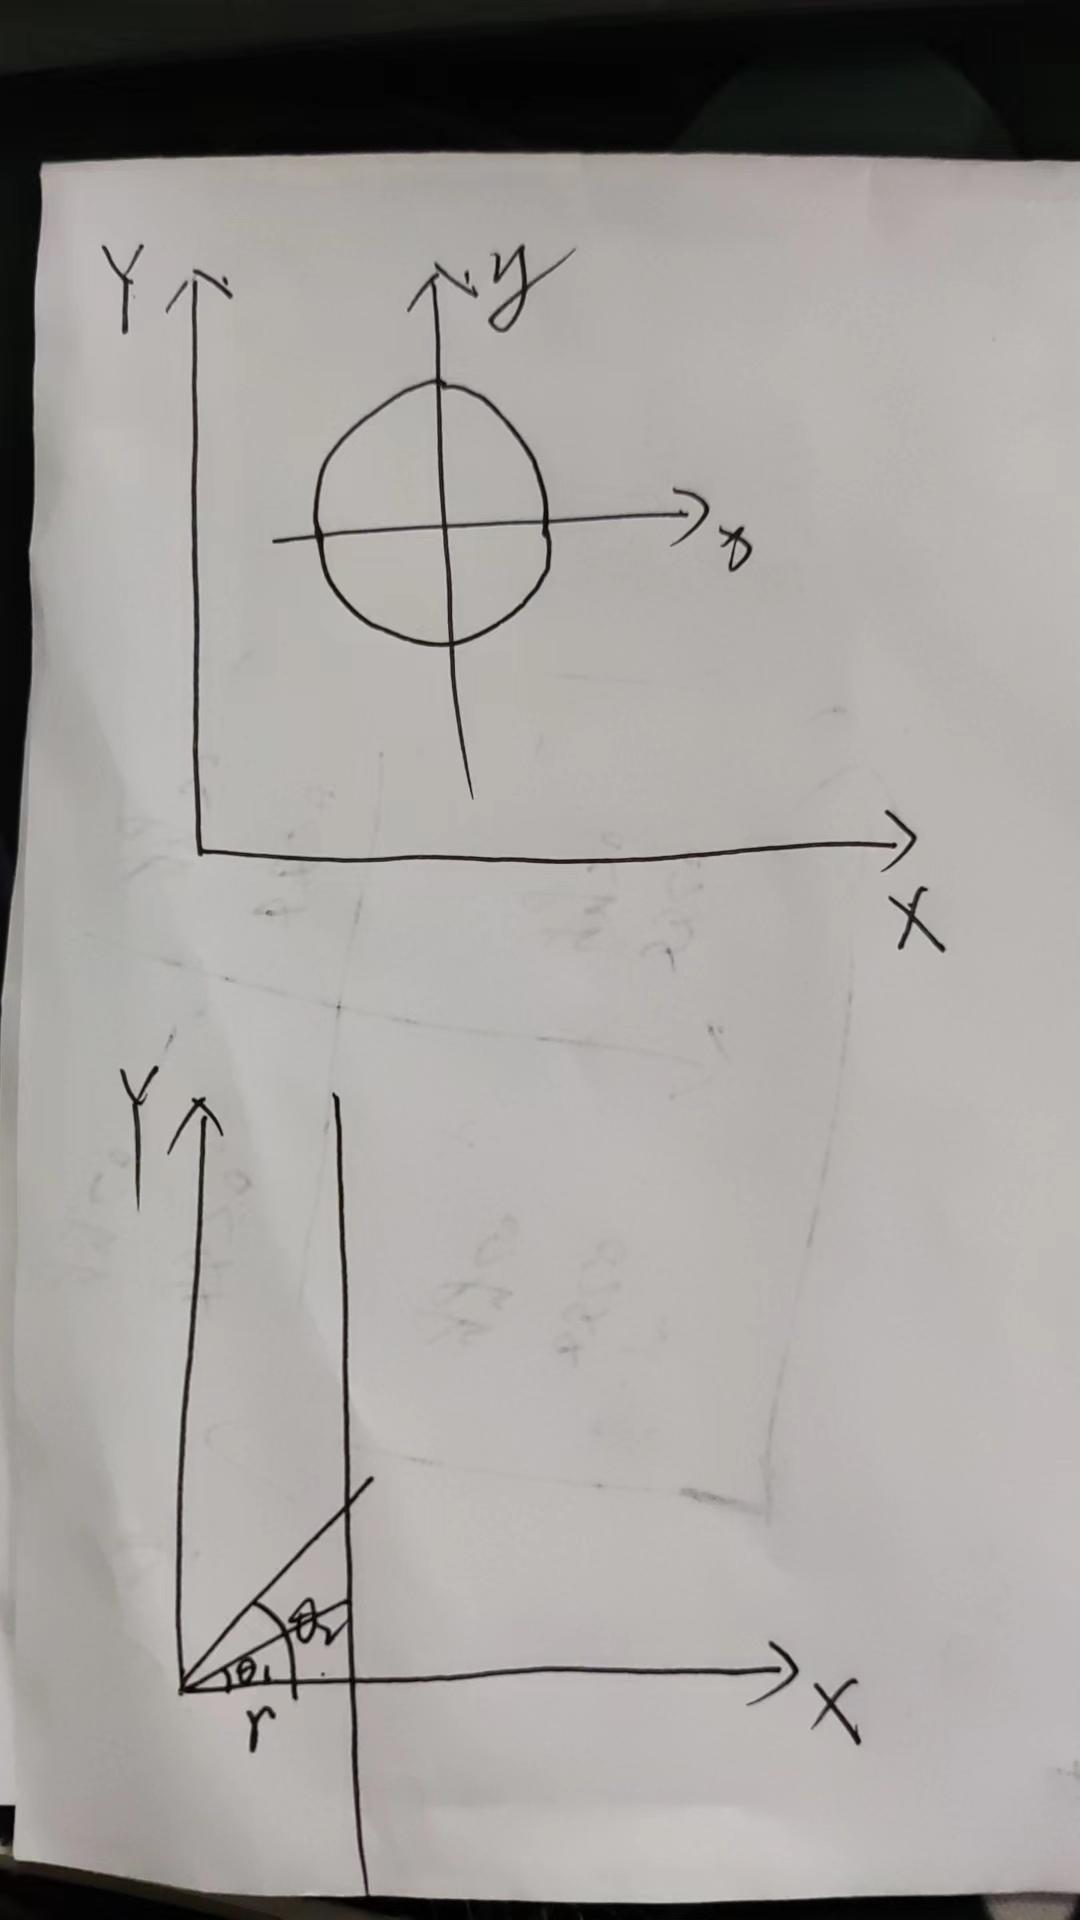

结果贴上

原图